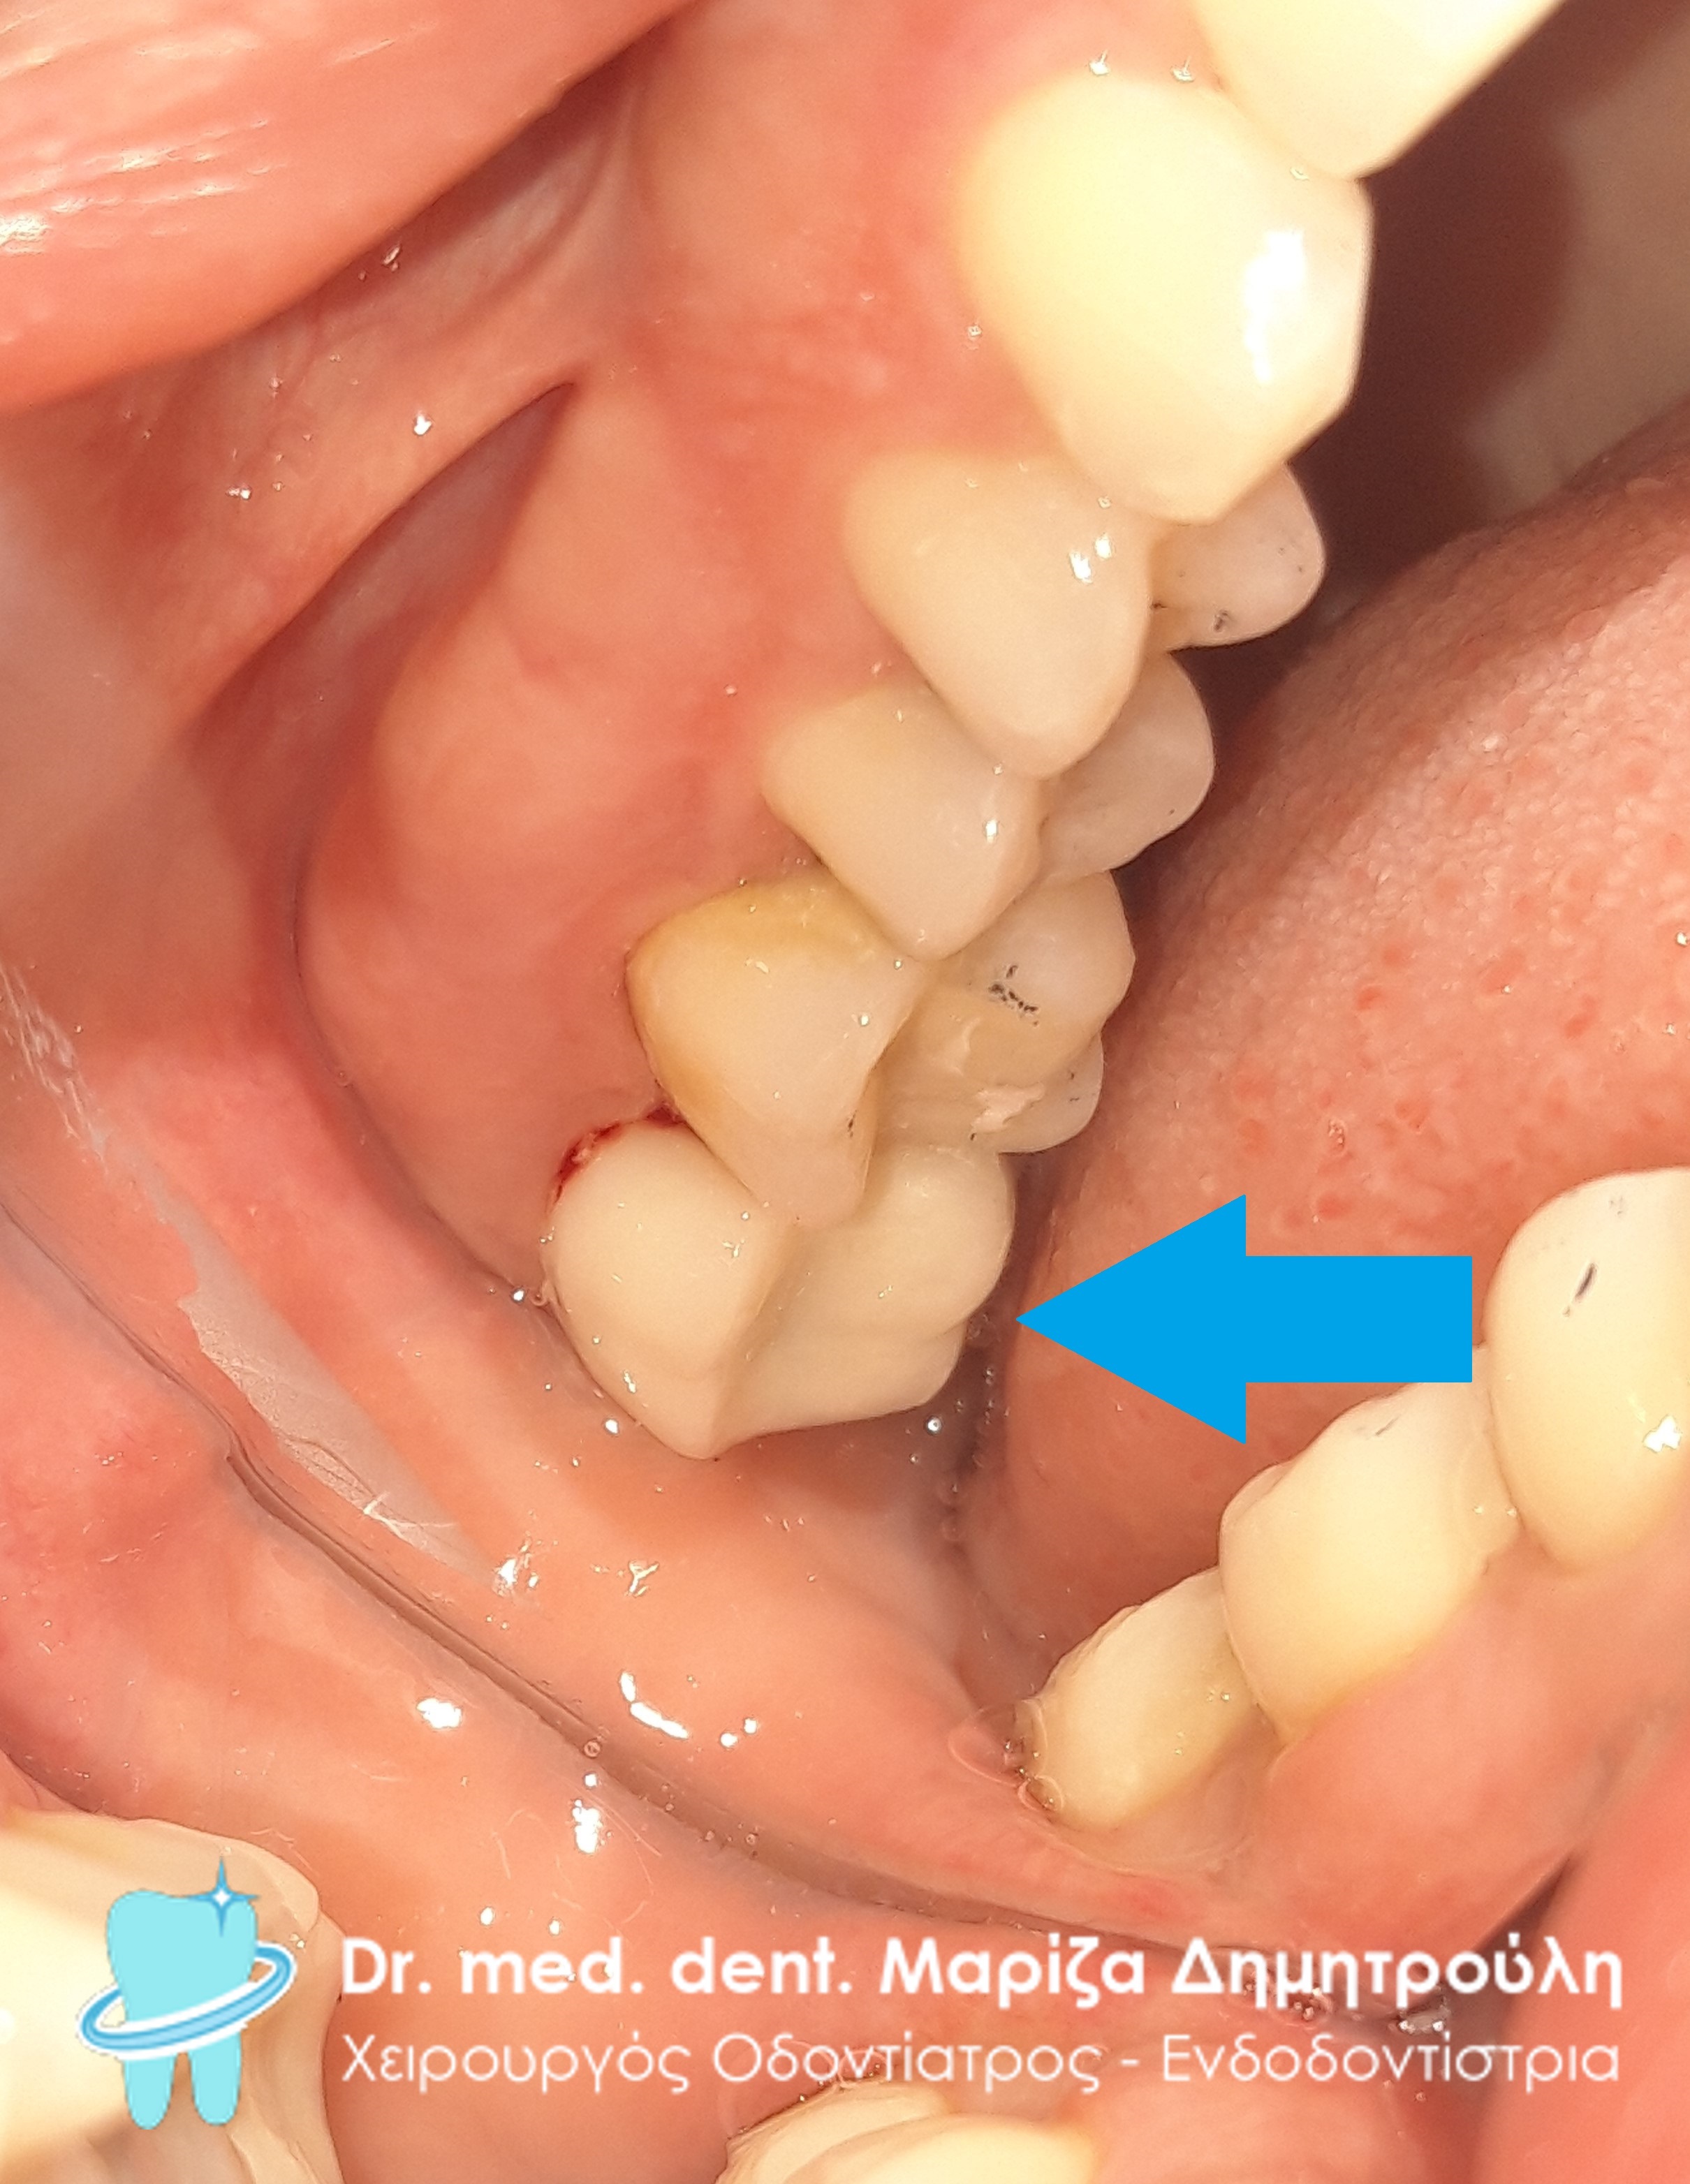

Η ασθενής έχασε το δεύτερο αριστερό γομφίο της κάτω γνάθου. Δεν επιθυμούσε να τοποθετήσει εμφύτευμα στην περιοχή, γιατί φοβόταν τη χειρουργική διαδικασία. Σε συνεργασία με τον οδοντοτεχνίτη αποφασίστηκε η κατασκευή μιας ολοκεραμικής θήκης, η οποία θα είχε ένα επιπλέον γομφίο “κρεμαστό” . Η συγκεκριμένη προσθετική αποκατάσταση αποτέλεσε μία εναλλακτική λύση θεραπείας στο πρόβλημα της ασθενούς, προκειμένου να αποφύγει τη χειρουργική διαδικασία του εμφυτεύματος.

Περιστατικό – Ολοκεραμικές θήκες / στεφάνες δοντιών με πρόβολο (κρεμαστό) στην κάτω γνάθο